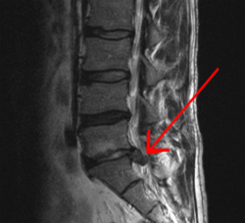

Lumbalgia o hernia discal

Lumbalgia o hernia discal, són unes de les patologies més freqüents en la nostra consulta. – El 70-80% dels individus poden tenir com a mínim un episodi de dolor lumbar en la seva vida. És un dels motius més freqüents de consulta mèdica i la segona causa de baixa...

Un osteòpata tracta la lumbàlgia

Sovint desconeixem que un osteòpata tracta la lumbàlgia, i actualment és un dels tractaments més eficaços.Fins al 85% de la població adulta ha patit alguna vegada lumbàlgia, un percentatge que pot variar en funció del país. És actualment la primera causa de baixa...